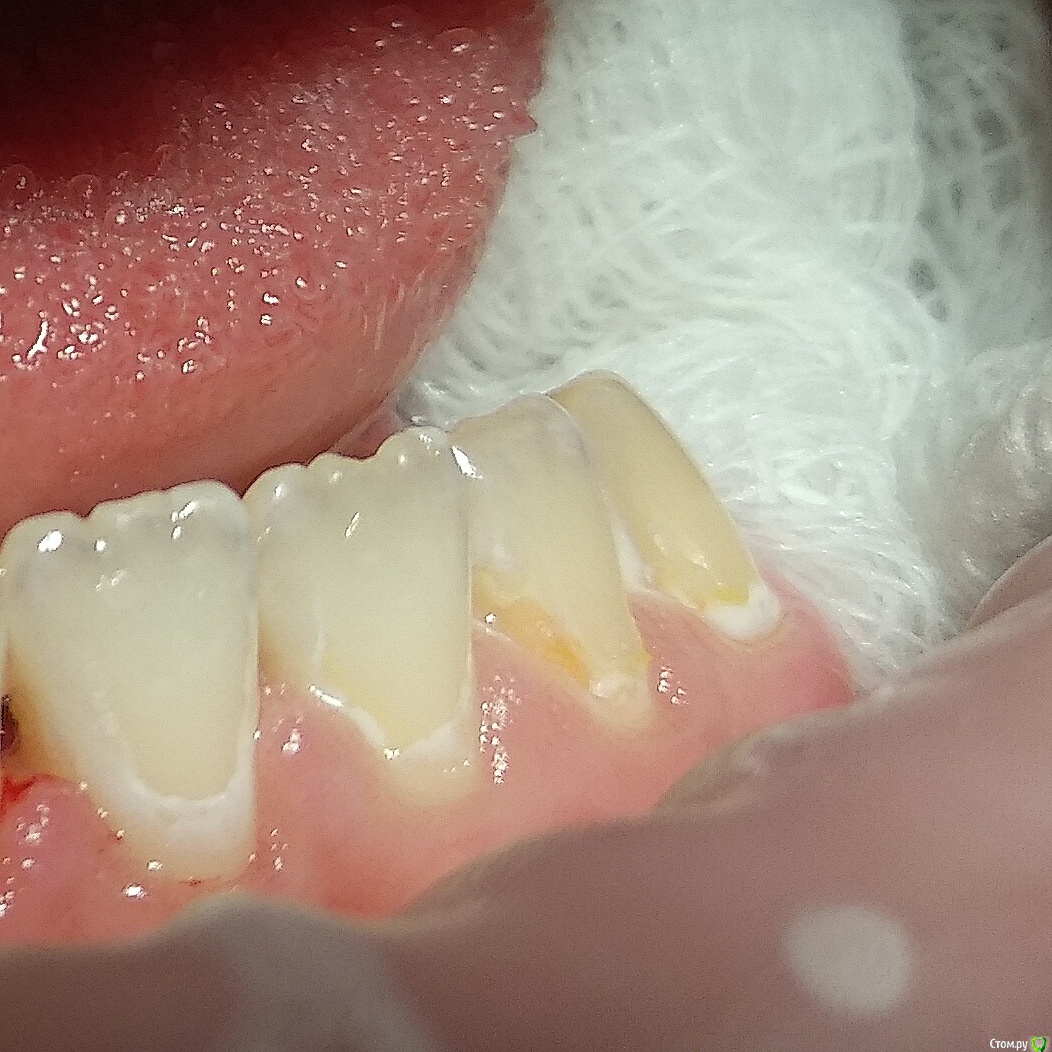

Paganini Опубликовано 13 октября, 2018 Поделиться Опубликовано 13 октября, 2018 (изменено) Приветствую! Помогите помочь пациенту (13 лет). Попросила ортодонта снять брекеты досрочно, потому что с эмалью беда - эмаль скалывается кусками, в местах под брекетами множественные дефекты. При нажатии на эмаль зондом остаются следы. Уверена, что до установки брекетов была уже патология (флюороз или гипоплазия), брекеты всего лишь усугубили ситуацию. С гигиеной тоже все плохо: всегда, когда пациент приходил ко мне на чистку, налета столько, что хоть ложкой снимай... Ставить пломбы? Дефектов очень много, и я думаю, что держаться это будет плохо, эмаль хрупкая. Сейчас комплексно укрепляем эмаль.P.S.: я не детский врач. Я гигиенист и терапевт с небольшим опытом работы. Изменено 13 октября, 2018 пользователем Paganini Ссылка на комментарий

Paganini Опубликовано 13 октября, 2018 Автор Поделиться Опубликовано 13 октября, 2018 Пострадали почти все резцы и клыки, жевательная группа в порядке, но там мало что есть (первичная адентия). Ссылка на комментарий